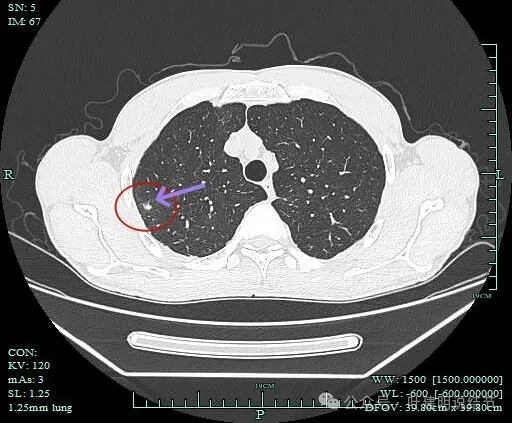

右上病灶1:

病灶出现,密度较高,不是圆形或类圆形,边缘略模糊。

病灶似乎有卫星灶,中间有小空泡征,边缘有晕。

感觉周围略糊,有晕的感觉。

上面层面密度较高。

似乎有毛刺征,但膨胀性不明显。

有部分边缘显毛糙。

点状高密度,有晕的感觉。

点状高密度结节。

点状高密度之外,蓝色箭头示周围有淡磨玻璃影。

风轻云淡磨成分明显且轮廓不清。中间的点状高密度显得不够致密,缺乏收缩力。

边缘区仍有淡磨形态的晕

此灶从连续层面上看,是自右上前侧斜行向左下后侧延伸的,整体病灶偏长条些,而且有晕、有淡磨成分,实性部分缺乏收缩力或膨胀性,更符合炎性病灶的恢复期或吸收不全的阶段。